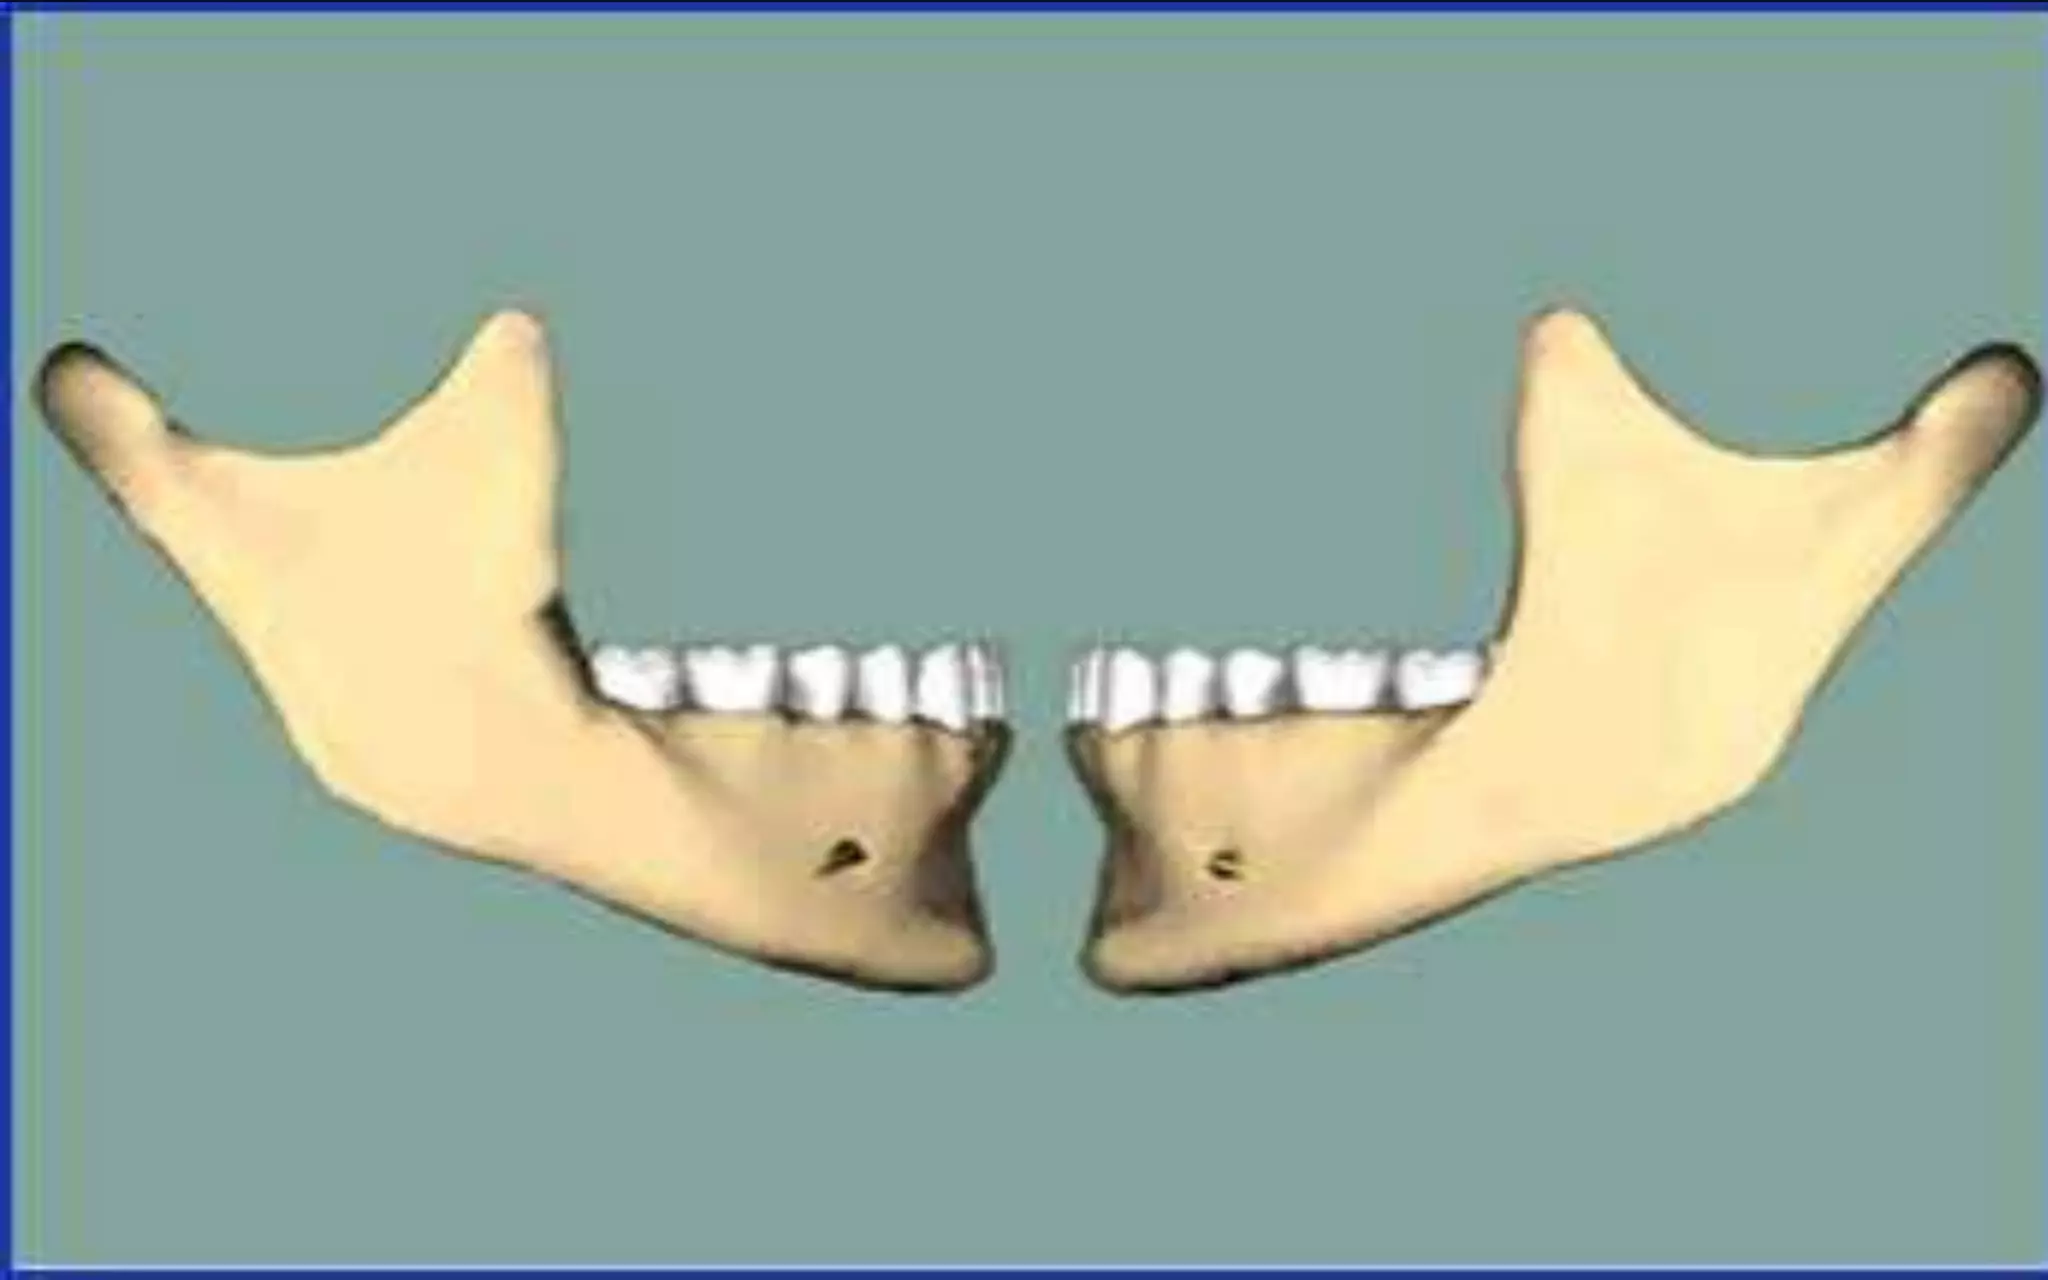

•2 lower molars missing

• Without the counter forces of the

bottom teeth , the top teeth supra

erupt

•With all teeth present there is stability.

Teeth are not actually rigid in the

mouth ,but stay in place due to

complex series of pressure contacts

and erruption forces

•Missing lower molar

•A single tooth loss in lower arch can

result in the tooth drifting forward

•This create poor contact and

periodontal (gum) problems

around the moving tooth